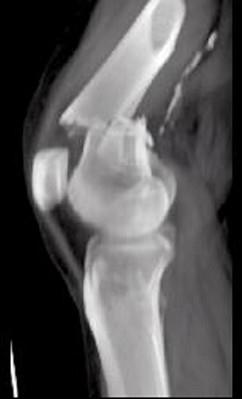

问题 男,45岁,车祸后左膝部剧痛,红肿,不能活动,请结合影像学检查,选出最可能的诊断 ( )

选项 A、胫骨骨折 B、腓骨骨折 C、股骨下端骨折 D、柯莱斯骨折 E、股骨颈骨折

答案 C